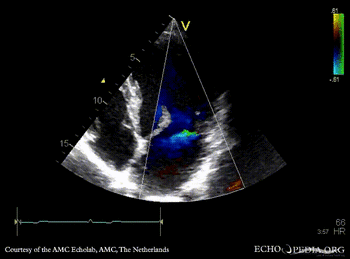

| Marfan Syndrome

| PLAX with Color Doppler: mild mitral regurgitation